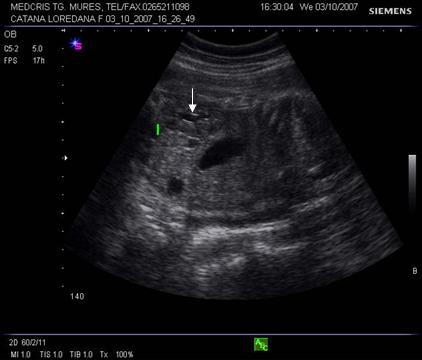

Fig. nr .279. Sarcina de 32 sapt., cu bazinet renal minim dilatat. ( cu linia rinichiul pol inferior,cu sageata pielonul )